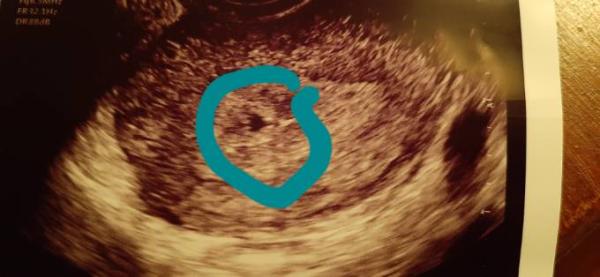

Huhu Mädels! :) Heute war es endlich soweit. Nach kurzem Gespräch samt Untersuchung gab es auch direkt einen Ultraschall. Alles genauso wie es sein soll. Sieht wie bei meinem Sohn aus außer das diesmal eine andere Stelle in der Frucht Höhle belegt wird. Laut Rechnung vom ES bin ich 5+6 der US sagt 6+0. bin gespannt was im ersten richtigen Ultraschall dann bei rum kommt. Nächste Woche geht es zum Blut abnehmen, da ich so ein spezieller Fall bin muss es auch der Arzt machen. Die Arzthelferin traut sich nicht, aber das kennen die bereits. Im November hab ich dann meinen ersten Termin in der Hebammenpraxis meiner Hebamme. Sie hatte ich auch bei meinem Sohn. Bin gespannt auf eure Berichte vom ersten Ultraschall. Lg Clee

Bild zu Erster Frauenarzttermin - Forum für Juni - Mamis

Das ist doch ganz toll! Schönes Bild hast du da heute bekommen.